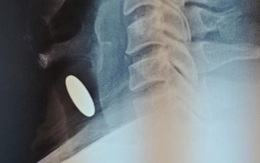

Suýt chết vì đồng xu lọt vào cổ họng khi chơi đùa với con

TTO - Chơi đùa cùng con nhỏ, người đàn ông ở TP Nha Trang (Khánh Hòa) vô tình bị đồng xu lọt vào cổ họng. Trong lúc hít thở nhanh, đồng xu đi sâu vào bên trong khí quản, bịt đường thở.